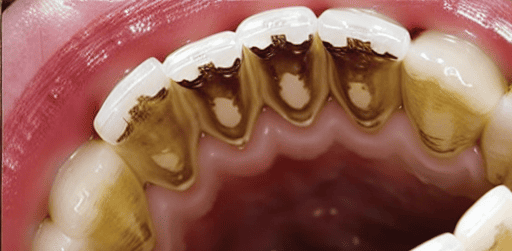

At the organ level, editing difficulty varies significantly. Regions such as the spine and bones (e.g., CT scans) remain especially challenging, with the best EA only reaching 0.38. This difficulty is not primarily due to grayscale input but rather the inherent structural complexity of bones. Unlike soft tissues, bones follow rigid, geometrically consistent patterns (e.g., aligned vertebrae, symmetric ribs), making even small editing errors visually salient and disruptive. For example, in a task like “correct spines”, the model must straighten the spine without disturbing rib symmetry or vertebral alignment, demanding a much higher degree of structural precision than tasks such as “remove intestinal polyps”. The largest performance gaps between Gemini and open-source models are seen in teeth (34%), hands (64%), and gastrointestinal tract (43%), further reflecting the challenges posed by complex anatomical structures and repetitive patterns. Conversely, superficial structures such as hair and nose are easier to edit, where ICEdit achieves strong performance (hair: EA = 0.71, VQ = 0.79).

| Remove stains, tartar, or plaque from teeth. | 22 | |